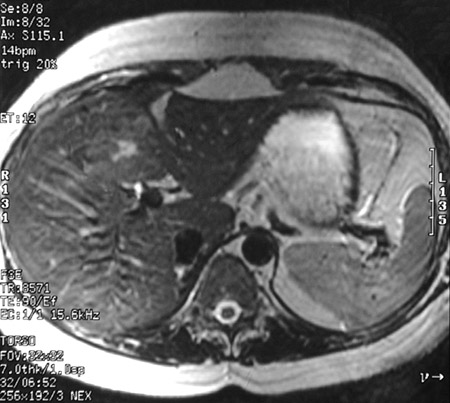

| The abdominal MRI scans in axial view above (T1 weighted) and below (T2 weighted) reveal an area of abnormal signal in the medial aspect of the right lobe of liver with a central bright scar. This is focal nodular hyperplasia (FNH), a slow-growing, hamartomatous process that is uncommon. It occurs more often in women than in men. |